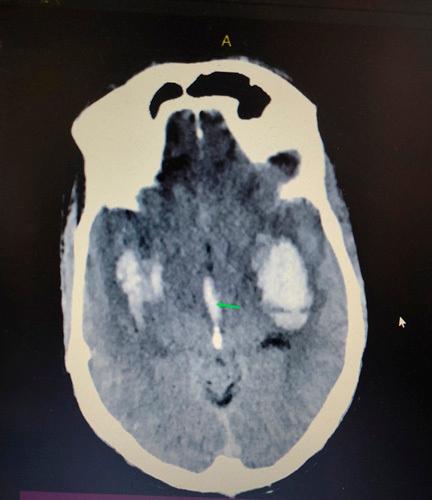

Twenty-three-year-old male with no prior comorbidities presented to emergency with sudden onset loss of consciousness and 1 episode of seizure. No history of intoxication or trauma was given. Glasgow Coma Scale at presentation was E1V2M2. CT scan head revealed bilateral basal ganglia haematoma along intraventricular haemorrhage.

一名23岁无既往合并症的男性因突发意识丧失和1次癫痫发作就诊于急诊科。无中毒或外伤史。就诊时格拉斯哥昏迷量表评分为E1V2M2。头颅CT扫描显示双侧基底节血肿伴脑室内出血。